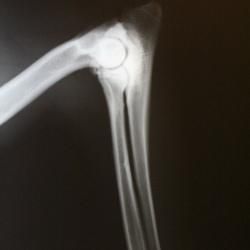

Hunden skal være fyldt 1 år, før den kan få vurderet sine albuer ved en AD-fotografering. Hunden bedøves let, og der tages et billede af hvert albueled i bøjet position, mens hunden ligger i sideleje.

Albueledsdysplasi (AD) vurderes efter en skala fra 0 til 3, hvor 0 er AD-fri og 3 er svær AD.